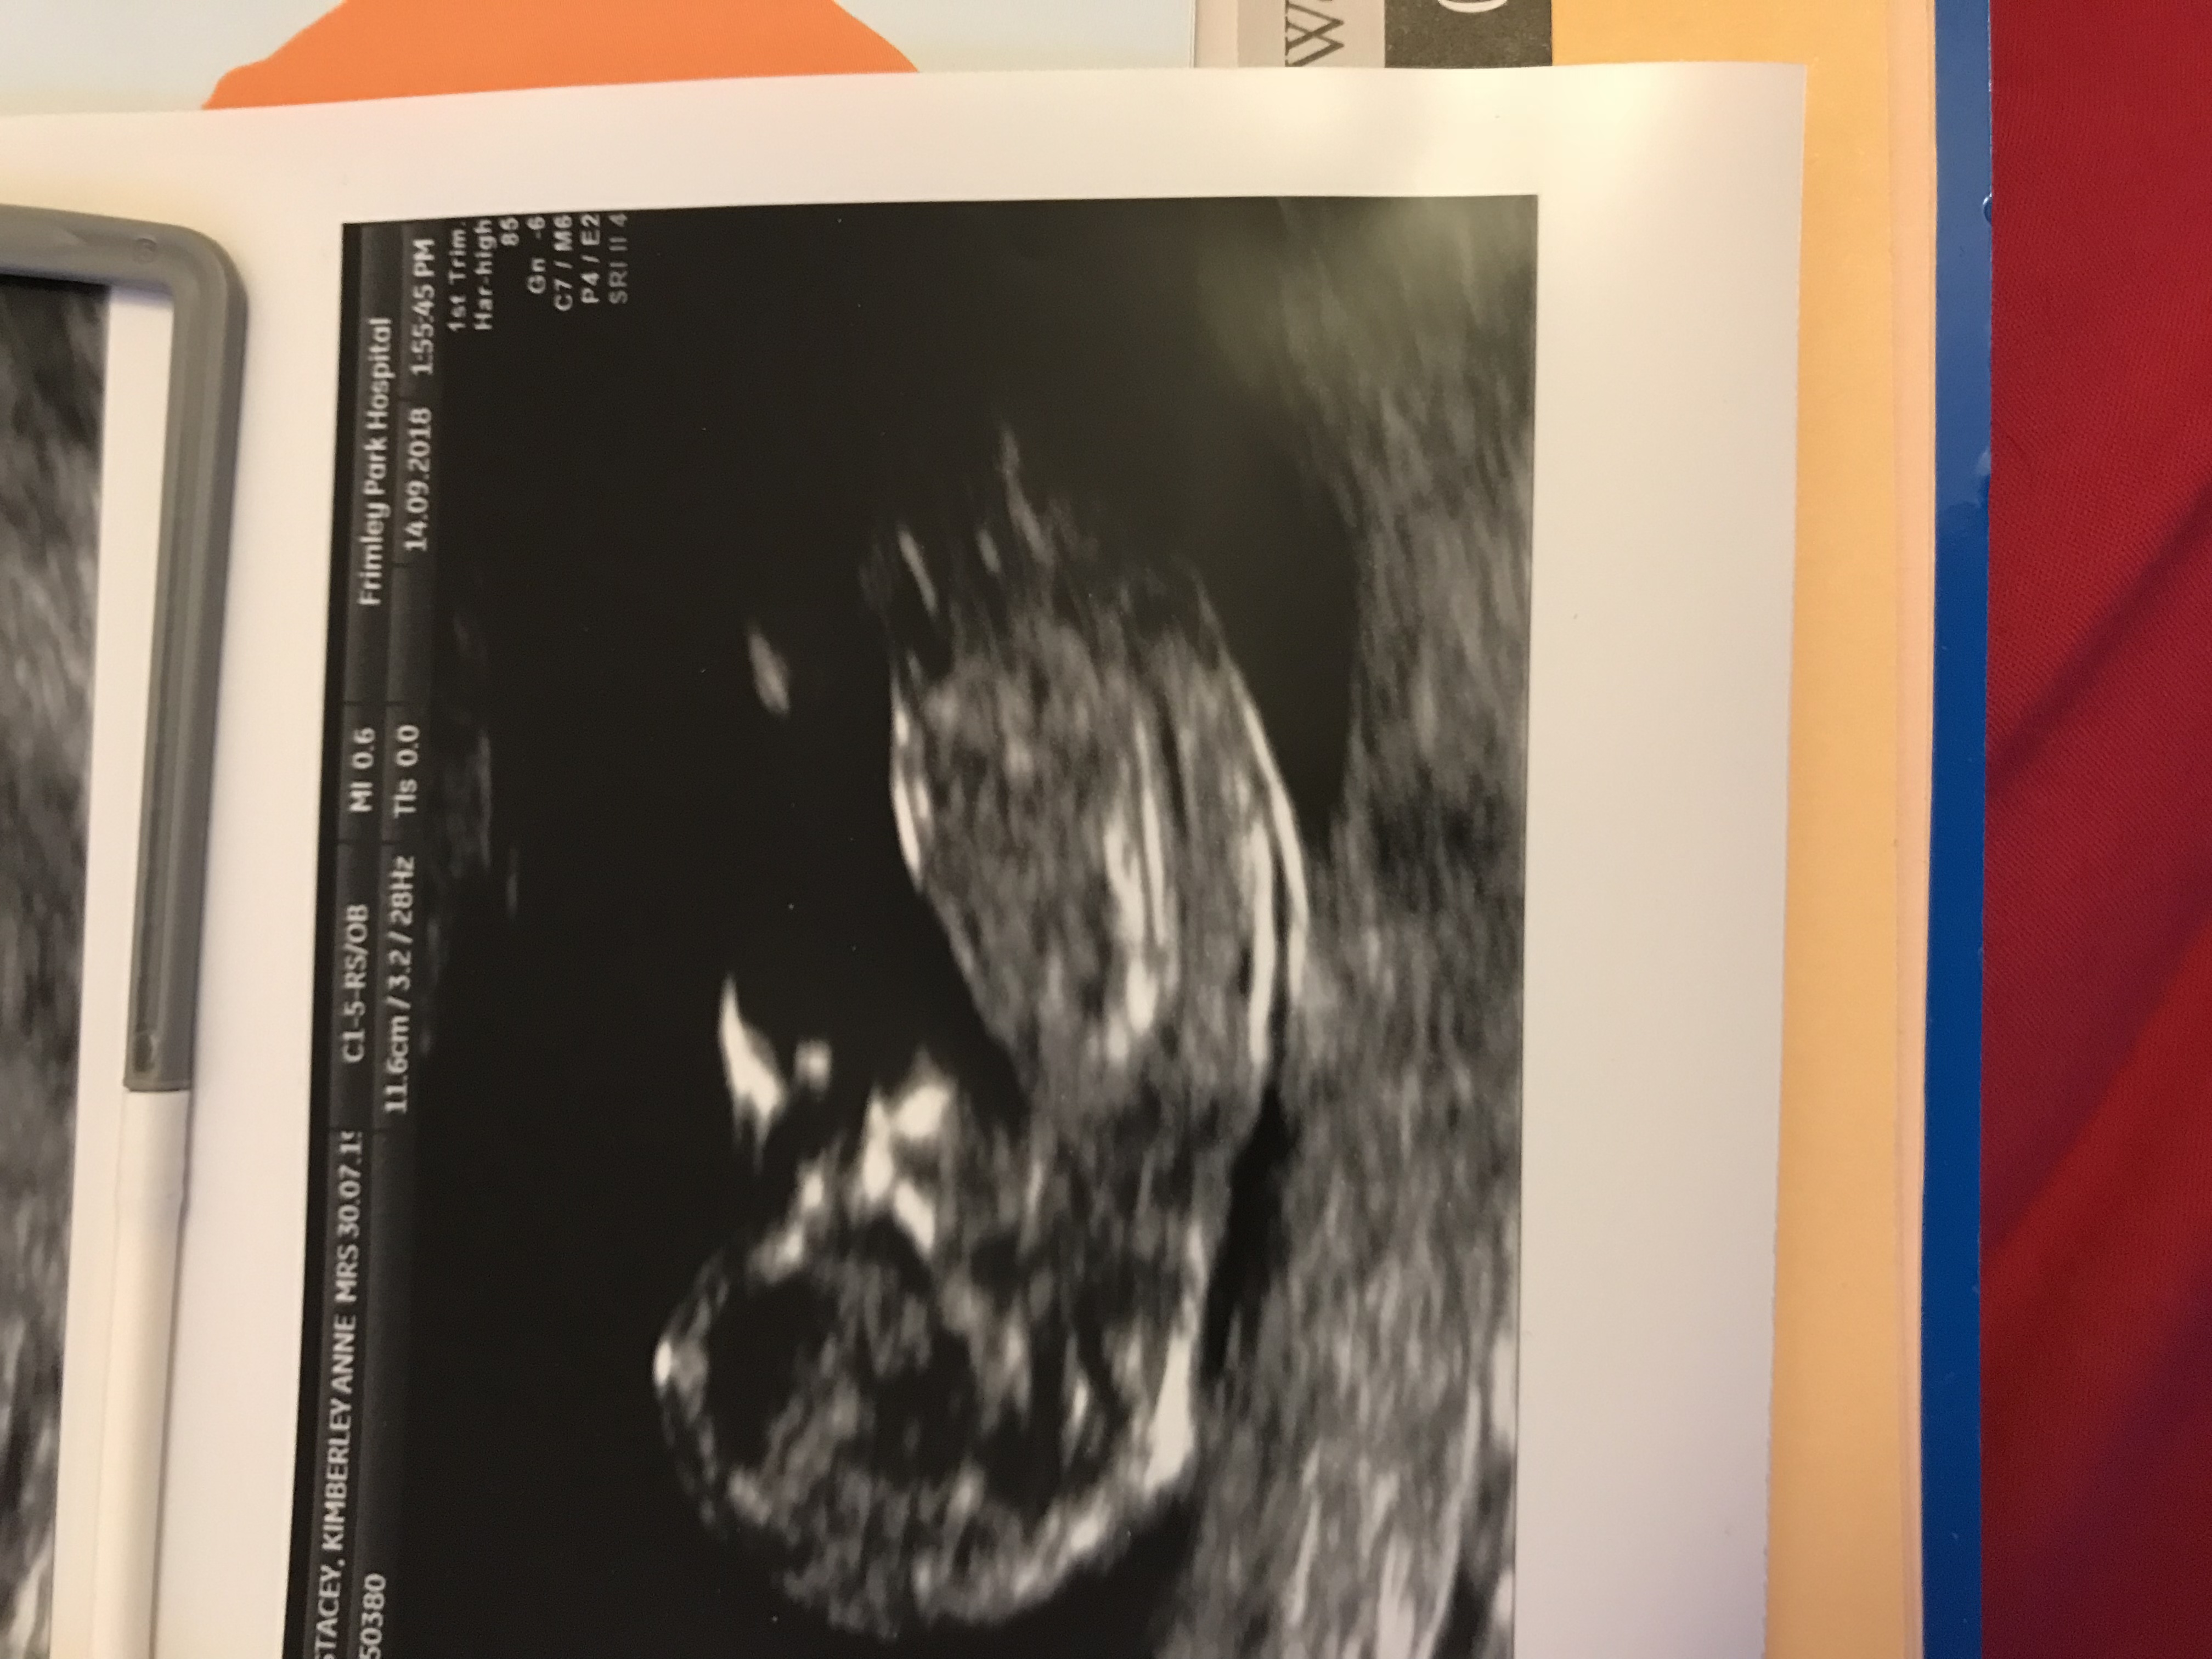

Hi there This is my 12 week scan picture can anyone make a guess on the gender please? Attachment 40390

Another pic